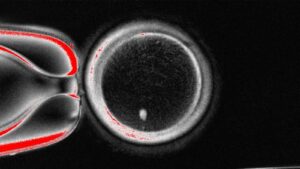

New Insights into Placenta Accreta Spectrum Biology

From Lab to Light: Saskia Baden’s Darkroom Portraits Illuminate Reproductive Science

This year, our Artist-in-Residence, Saskia Baden, completed her final project with us—anevocative series of silver gelatin prints created in the darkroom using scientific images fromUCLA

New Behind the Scenes: The Making of Abyssal

We are thrilled to share a behind the scenes look of the making of Abyssal by Saskia Baden! This is the Center for Reproductive Science,